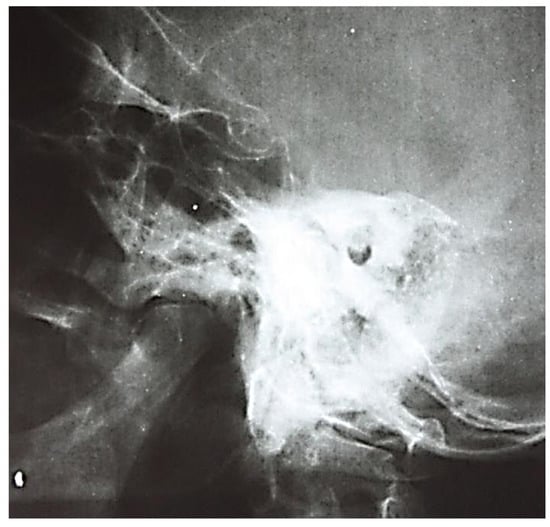

3.1.1. Conventional Radiology

3.1.2. Computed Tomography and Magnetic Resonance Imaging